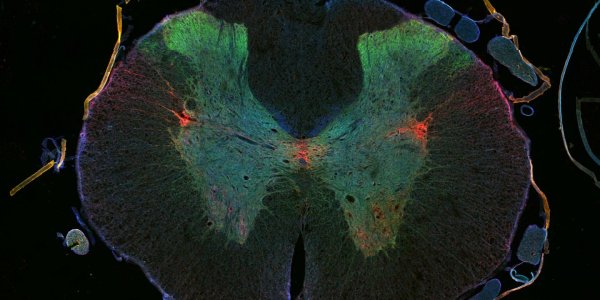

Mind Reading: Brain Activity Of Taste Decoded

A team of researchers can detect how taste is encoded in patterns of neural activity in the human brain. That means they can basically read your mind when it comes to food. Tastants in the mouth…